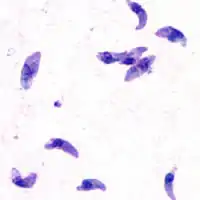

![]() Токсоплазмы при оптической микроскопии | |